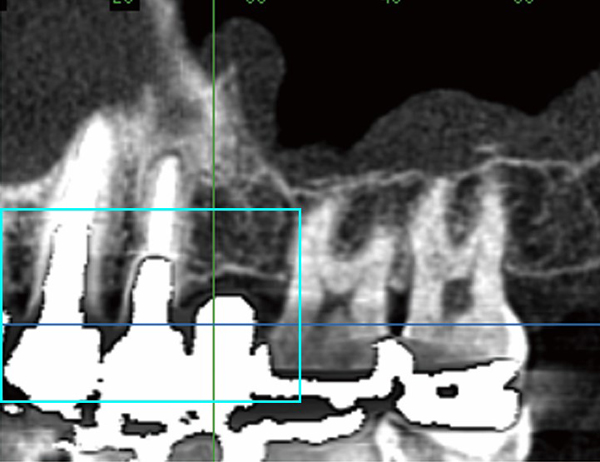

CT

当院では2014年1月より歯科用CTの設置をいたしました。

CTを導入したことにより、インプラント手術時のシミュレーションや診断はもちろん、親知らずの抜歯などの外科的処置や矯正治療、根の治療をする際にも、より正確な診断の元、より確実で安全な治療できるようになりました。

また、当院で導入しているCTは、他の歯科用CTではわからない骨質(骨の硬さ)についても正確に把握することができますので、インプラント治療を行う上では特に有効に活用できます。

他の歯科用CTは歯やあごの骨を立体的に把握することはできるものの、骨質(硬さ)について正確に把握することはできません。

一方で、当院の歯科用CTは骨質(硬さ)を正確に計測できるため、骨質(硬さ)を事前に把握しておくことが重要であるインプラント治療に特に有効です。当院の歯科用CTは数ある歯科用CTの中でも特に優れた性能を持つ装置です。

口の中は体の他の部分とは違い、歯の詰め物や被せものとして金属があります。金属はX線を通しにくいため、その影響でこれまでのCTでは周りの骨の状態が把握できないことがありました。

当院の歯科用CTは金属の影響を除去するプログラムを搭載していますので、他のCTでは金属の影で映らない部分の骨でも診断することができます。